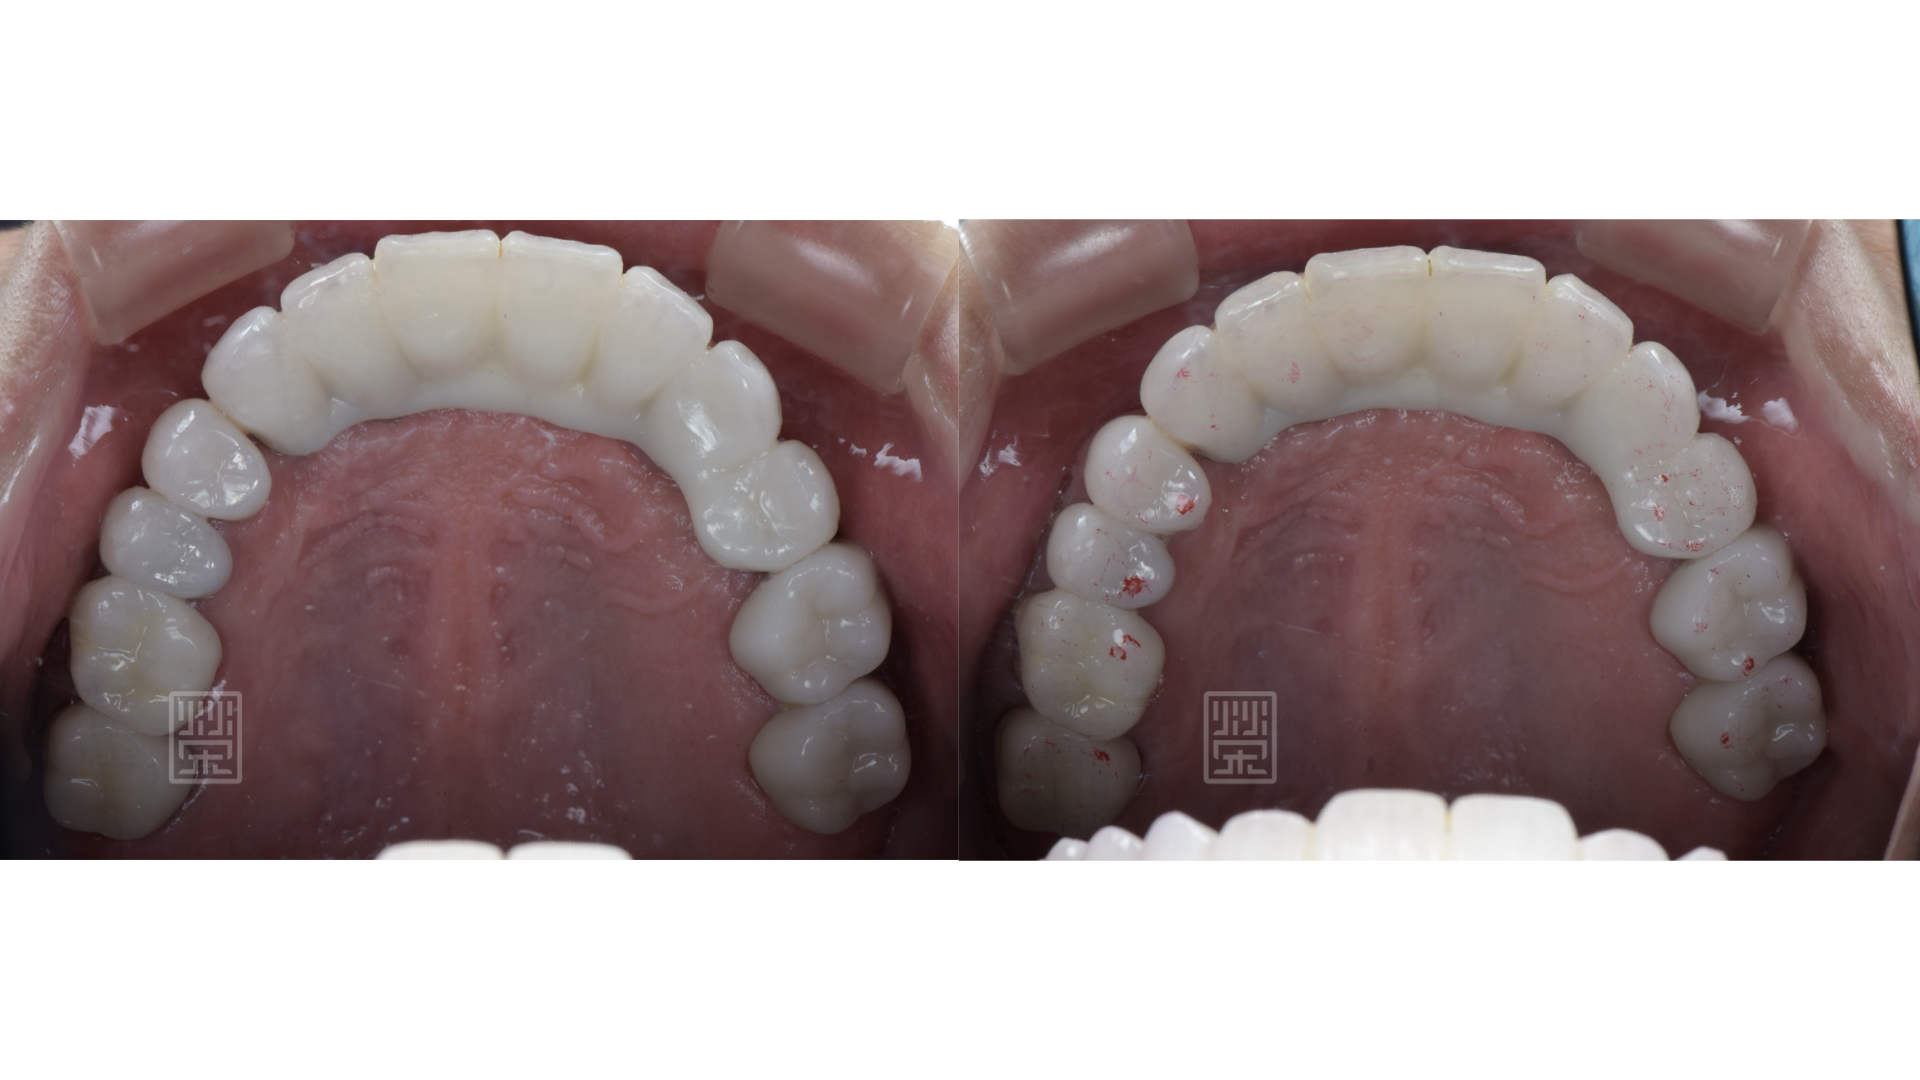

預計增加上顎門牙長度,先將下顎門牙用樹脂恢復原本型態,將貼片的空間先保存起來

藉由矯正,將下顎們牙齒軸拉正

矯正後,再將門牙拉長,達到理想的牙齒的長度